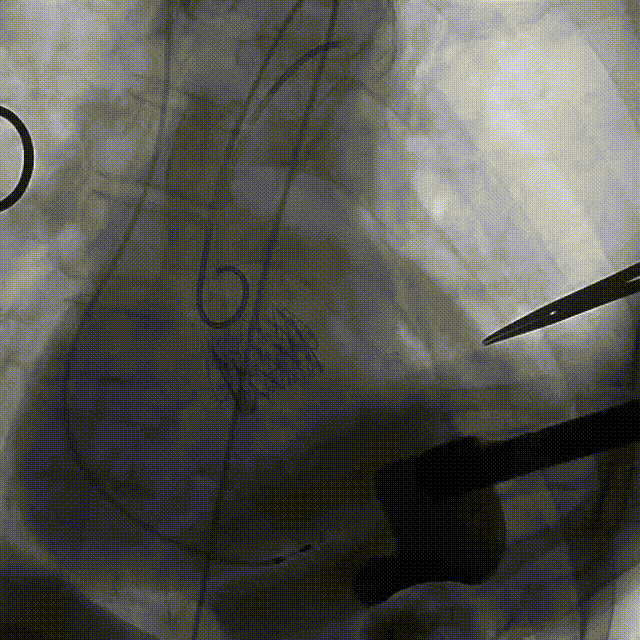

近日,中国人民解放军南部战区总医院王显悦教授、张本教授团队应用J-VALVE瓣膜完成一例高难度经心尖TAVI。患者为72岁男性,心脏超声示主动脉瓣重度狭窄伴轻度关闭不全,且二尖瓣中度狭窄。由于具有急性心力衰竭、高血压3级、肺气肿等其他疾病,且体重仅35公斤,对外科开胸手术耐受较差,风险极大,经过团队综合评估,决定行经心尖TAVI手术,拟植入25mm J-VALVE瓣膜。该患者存在升主动脉瓷化和左室流出道重度钙化,为手术增加了额外难度,术者团队凭借过硬的专业技能和细节处理能力,有效避免了术中可能存在的风险,并成功植入瓣膜。术后食道超声示无瓣周漏、无冠脉堵塞等并发症,患者症状明显缓解,手术顺利完成。

该患者升主动脉瓷化,左室流出道重度钙化。在TAVI手术过程中,导管和瓣膜的通过可能会对瓷化主动脉造成损伤,增加主动脉夹层、血管破裂等严重并发症风险;左室流出道的重度钙化会影响人工瓣膜与周围组织的贴合,使得瓣膜无法完全密封,从而增加瓣周漏的发生概率。

手术过程